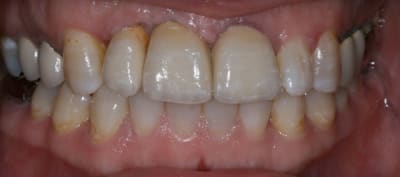

On avance dans le cas, j'ai revu la patiente hier.

Elle est satisfaite et moi pas vraiment, comme quoi...

Elle ne veut pas faire de chir mucco gingivale et accepte éventuellement que je fasse une petite chir d'élongation coronaire sur 21 car elle trouve cela surperflux.

Tristesse et difficulté des sourires gingivaux !

J'avais bien raison de me méfier au départ...

Dommage pour la teinte...

Une greffe osseuse aurait bcp aider, les implants sont trop enfouis par rapport à la 21.

Dans les cas où l'esthétique est en jeu, de 13 à 23, C'est le niveau osseux des dents adjacentes qui dicte le plan de traitement. Un point de contact très gingivale aurait probablement amélioré le cas à long terme entre 13 et 12 sur implant, il ne semble pas y avoir de contatc?? High lip line... encore plus demandant.

Je suis persuadé que si ton prothèsiste réussit à reproduire la richesse des petits défauts de ses propres dents sur tes dents en céramique , ce serait et ça passerait bcp mieux

Je crois que finalement ces trois trop jaune et quasi monolithique ds leur couleur est vraiment la chose la plus atroce

Bon finalement je vous poste le cas terminé.

La prochaine fois je ferrai une greffe d'apposition comme j'avais pu le préssentir... Ca me permettra de garder les papilles.

A la prochaine séance je gomme la coloration mésiale de 12, c'est promis ;+)

Un cas pas évident... l'important est que la patiente soit contente à la fin.